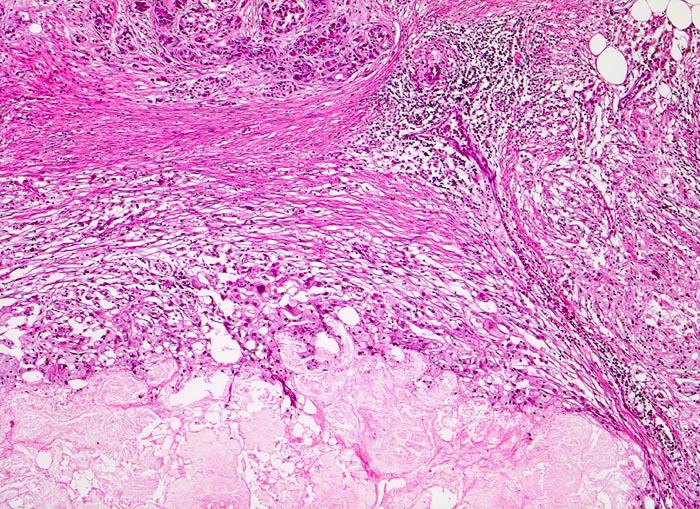

Chronisch-sklerosierende Pankreatitis mit älterer Nekrose

Anschnitt eines fibrosierten Läppchens. Daran angrenzend eine breite Sklerosezone mit lockerem chronischem Entzündungsinfiltrat. Unten im Bild eine alte, lytische Gewebsnekrose als Überbleibsel eines akuten Pankreatitisschubes.

Alkoholiker mit rezidivierten akuten Pankreatitisschüben. Chronische Diarrhoe.

Die chronische Pankreatitis bei Alkoholikern verläuft meist schubweise.